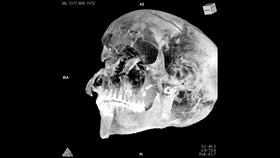

Previous studies and X-rays of his remains noted the king had severe headwounds, but not other wounds on his body, leading to the theory he had been captured in battle and executed afterwards, possibly even by the Hyksos king himself. The poor condition of the mummy also suggested the embalming was a hasty job not fit for the epic royal mummification rituals and techniques.

Now, CT scans have revealed new details of these head injuries, including wounds not described before, concealed by the embalmers’ efforts. Analyzing these new details, the researchers have formulated a new theory of the pharoah’s last hours. They posit Seqenenre was indeed captured on a battlefield, but had his hands tied behind his back so he couldn’t defend himself against his attackers.

The CT scans and other evidence suggest the execution was carried out by multiple attackers, as the wounds matched at least five different known Hyksos weapons.

The CT scans also showed that what had been thought about the poor mummification job may not be true. The details showed it was skillfully done, using embalming material as fillers to hide the king’s head wounds similar to today’s plastic surgery. This suggests the mummification took place at a proper laboratory rather than a poorly equipped place.